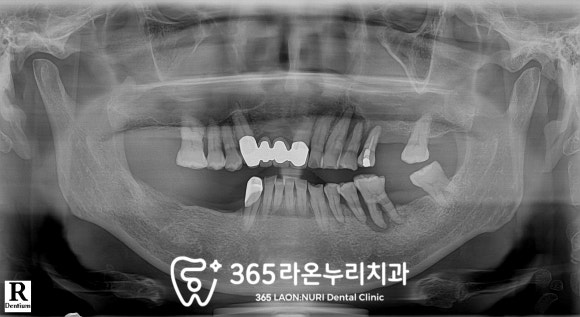

파노라마에서 보이는 것과 같이

자연치가 결손된 부위가 있어

오른쪽으로는 식사를 잘 하지

못하시는 상황이었으며

이외에도

치주 질환으로 잇몸뼈가 녹고

뿌리 끝에 염증이 생겨있는 이도 있었습니다.